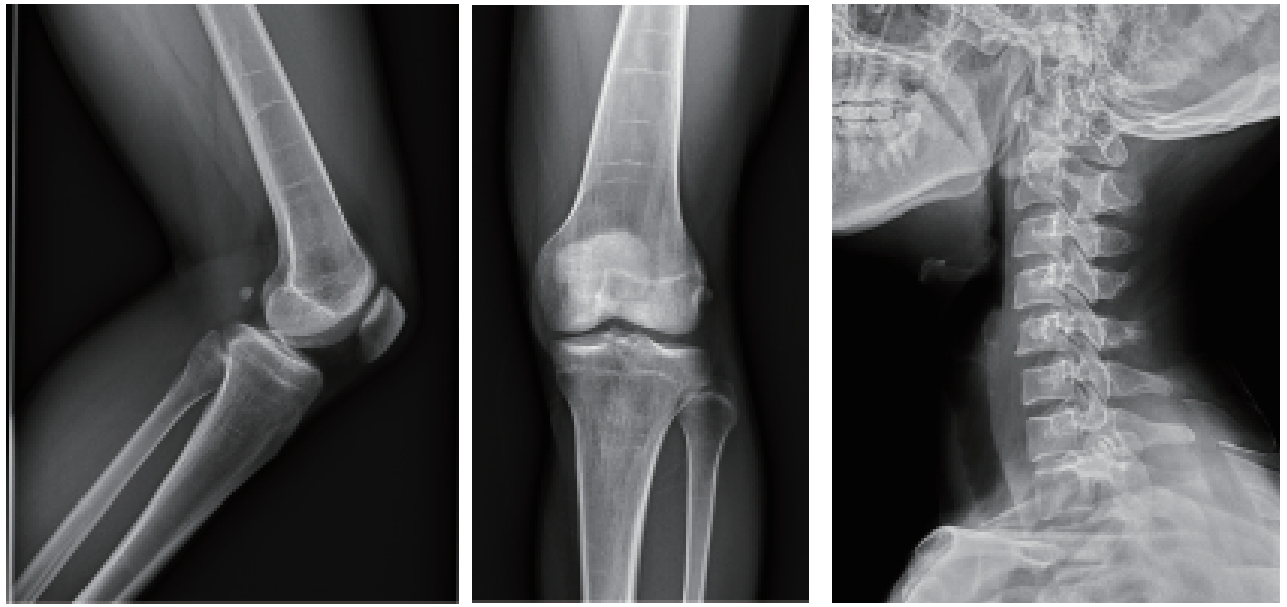

数字化摄影:

为全身各部位摄影,包括常规立位、卧位摄影等(如胸片、颈椎、腰椎、腹部等)和特殊倾斜、角度摄影(如髌骨轴位、跟骨轴位等)